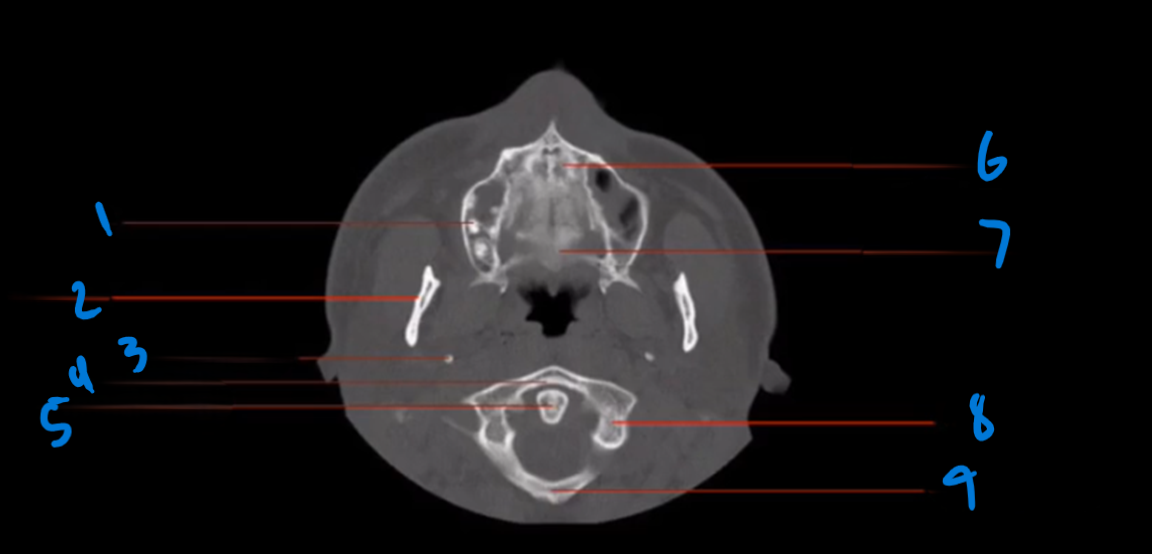

Landmark # 1

Tooth Root

Landmark 2

Mandible

Landmark 3?

Styloid Process, Temporal Bone

Landmark 4?

Anterior Arch, C-1

Landmark 5 ?

Odontoid Process, C-2

Landmark 6 ?

Hard palate, Maxillary bone

Landmark 7?

Hard Palate, Palatine Bone

Landmark 8?

Lateral Mass, C-1

Landmark 9

Posterior Arch, C-1